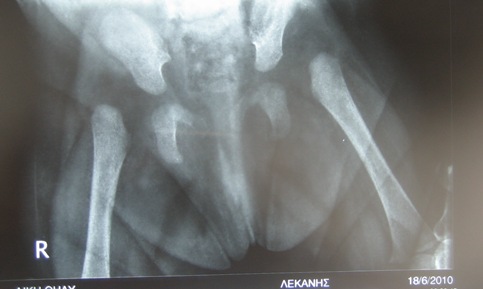

Ακτινολογική εικόνα εξαρθρήματος αριστερού ισχίου

Ο υπερηχογραφικός έλεγχος αποτελεί την ασφαλέστερη μέθοδο για την αντικειμενική καταγραφή της παθολογίας του βρεφικού ισχίου, ιδίως πριν την εμφάνιση των πυρήνων οστέωσης. Αποφεύγουμε την άσκοπη ακτινολογική εξέταση φυσιολογικών βρεφών.

Στον ακτινολογικό έλεγχο ελέγχουμε την συμμετρία των λαγονίων και των θυρεοειδικών τρημάτων.  Η διάγνωση της δυσπλασίας είναι ευχερής όταν έχουν εμφανισθεί οι πυρήνες οστέωσης.